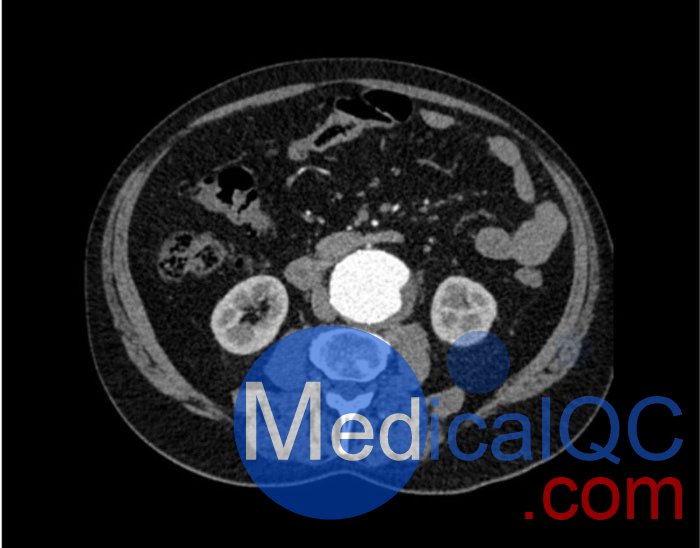

WEK53-05腹部模體,WEK53-05動脈瘤腹部模體,WEK53-05 CT血管造影模型模擬了動脈期的造影劑增強腹部。它覆蓋第一腰椎至第四骶椎。它有一個腎下腹主動脈瘤。

真實模擬脈管系統、骨骼和軟組織,包括肝臟、胰腺、脾臟、腎上腺、腎臟、胃、小腸和結腸。

肝硬化,膽囊切除術,下腔靜脈濾器,腎囊腫,腎結石,淋巴結。